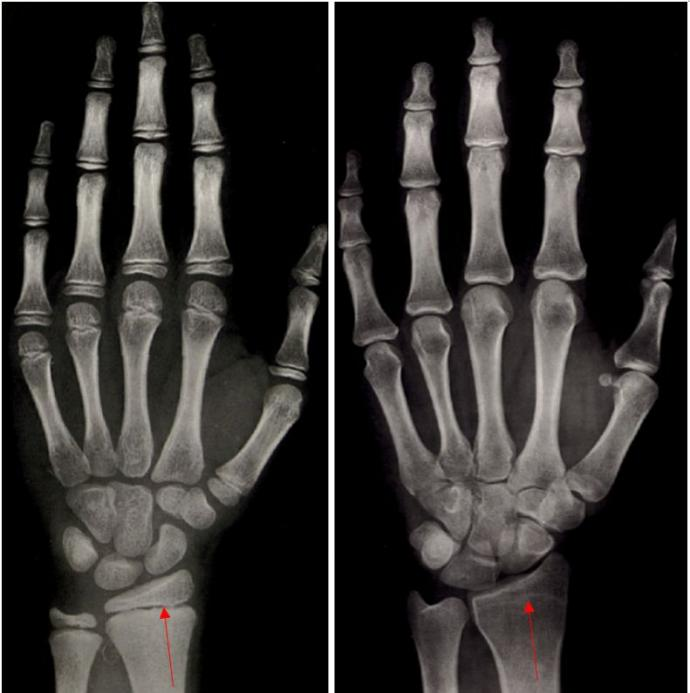

那么这里就会有人问,多少岁以后就不再长高了呢?这里就给大家献上我们儿童内分泌医生最经常做的检查:左手骨龄片。

左边这个是男性8岁7个月的骨龄片,右边是17岁的骨龄片,从8岁7个月的骨龄片上可以看到,红箭头所指的这个缝隙我们叫做骨骺,理论上说只要骨骺没有闭合,就说明还有生长空间;而右边17岁骨龄片中的红箭头所指的地方骨骺已经闭合,就可以判断基本不会再长高了。

(中国人手腕部骨龄标准—中华05及其应用)